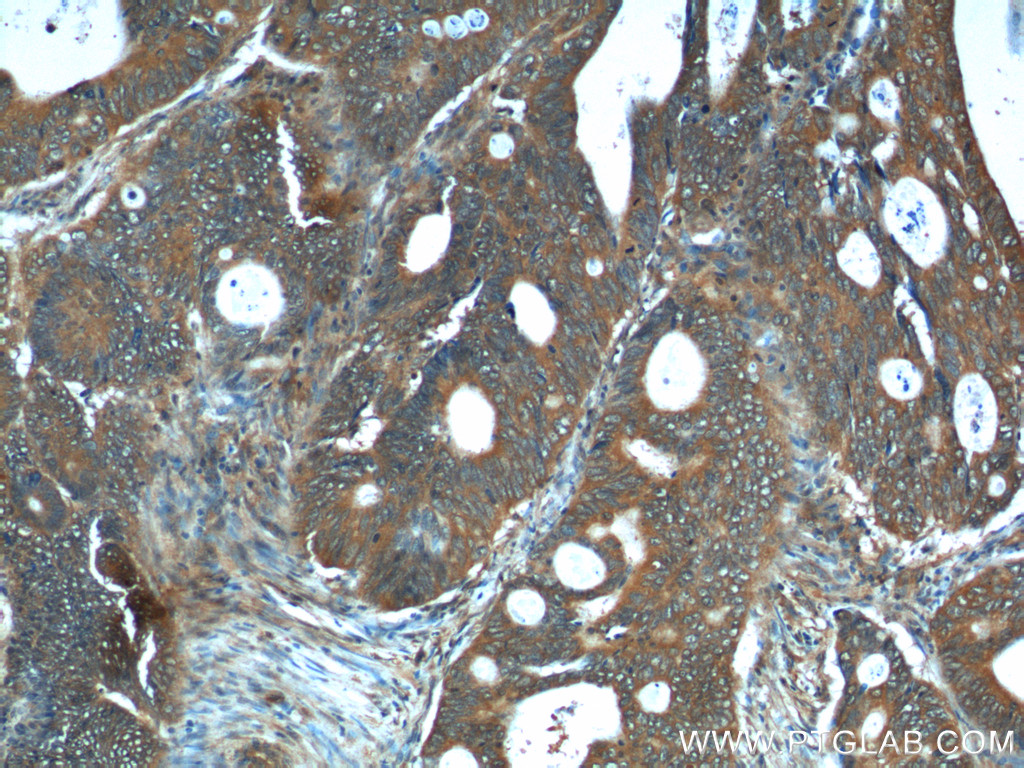

| Positive IHC detected in | human colon cancer tissue Note: suggested antigen retrieval with TE buffer pH 9.0; (*) Alternatively, antigen retrieval may be performed with citrate buffer pH 6.0 |

| Immunohistochemistry (IHC) | IHC : 1:50-1:500 |